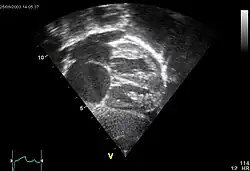

Mitralstenose

Klinik: Leistungsminderung durch die diastolische Füllungsstörung mit Reduktion des Herzzeitvolumens (HZV), Belastungsdyspnoe, spät: Facies mitralis („rote Bäckchen“), periphere Zyanose, Zeichen der Rechtsherzinsuffizienz, Tachyarrhythmia absoluta bei Vorhofflimmern.

Kompl.: Vorhofdilatation mit Vorhofflimmern und evtl. Vorhofthrombose und Embolie, Rückstau in die Lunge (Lungenstauung, Lungenödem) und ggf. bis in den großen Kreislauf (pulmonale Hypertonie, Rechtsherzbelastung/Cor pulmonale, Rechtsherzinsuffizienz), bakterielle Endokarditis.

![]() |